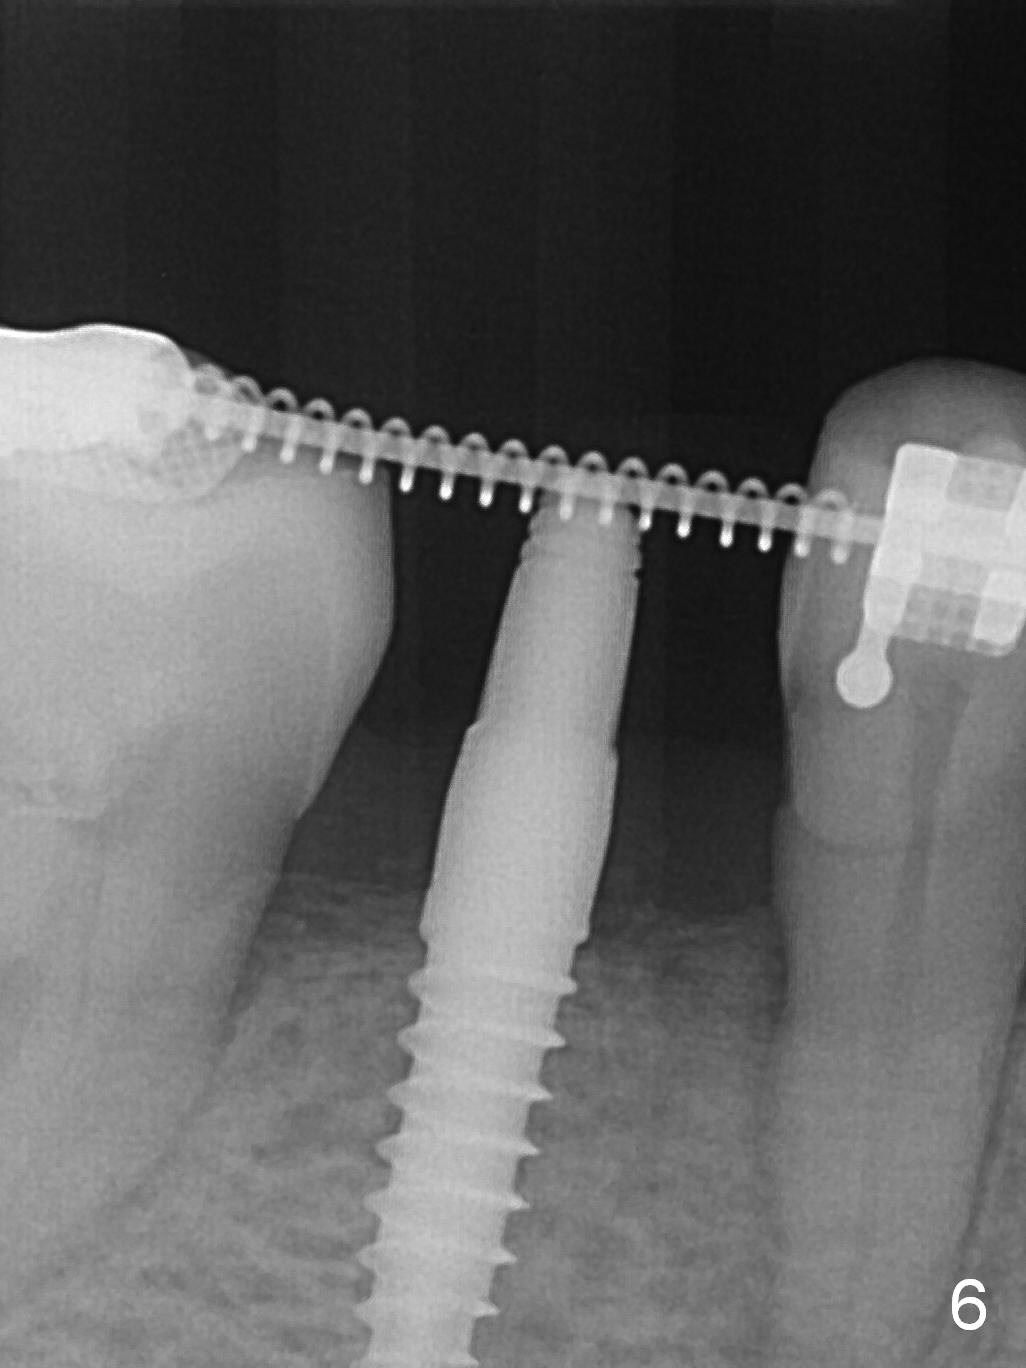

There is no bone loss 3 months postop (Fig.6).

Before crown cementation, the ridge looks wider (Fig.7 *) than preop. There is no diastema between #31 and 32 (Fig.8, 17 days post cementation). The patient is pleased with less food impaction. The total treatment (including ortho) is 16 months. It appears that distalization of #29 is not effective to gain the bone width. In fact simultaneous GBR with implant placement is much more efficient. There is no bone loss 3 months post cementation (Fig.9). The gingiva looks healthy 10 months post cementation (Fig.10). The implant crown is functioning 1 year 9 months post cementation (Fig.11) and 3 years 7 months post cementation (Fig.12).